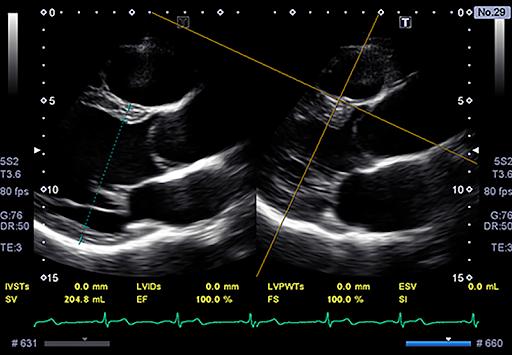

Flex-M Mode позволяет получать изображения в M-режиме с коррекцией угла наклона у пациентов, когда сложно получить изображение в M-режиме по оси.

PLAX-Parallel Measurement

Помогает в измерении диатолических и систолических параметров у пациентов с внеосевым видом на уровне сосочковых мышц по длинной оси.